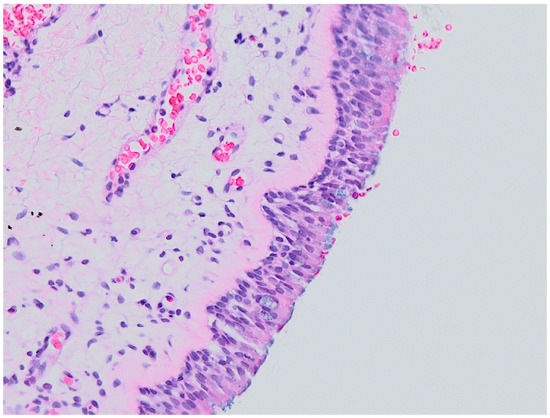

- 0

- Normal histology (no inflammation);

- 1

- Epithelial hyperplasia;

- 2

- Epithelial hyperplasia with mild signs of inflammation;

- 3

- Chronic inflammation.

3.2. Histology